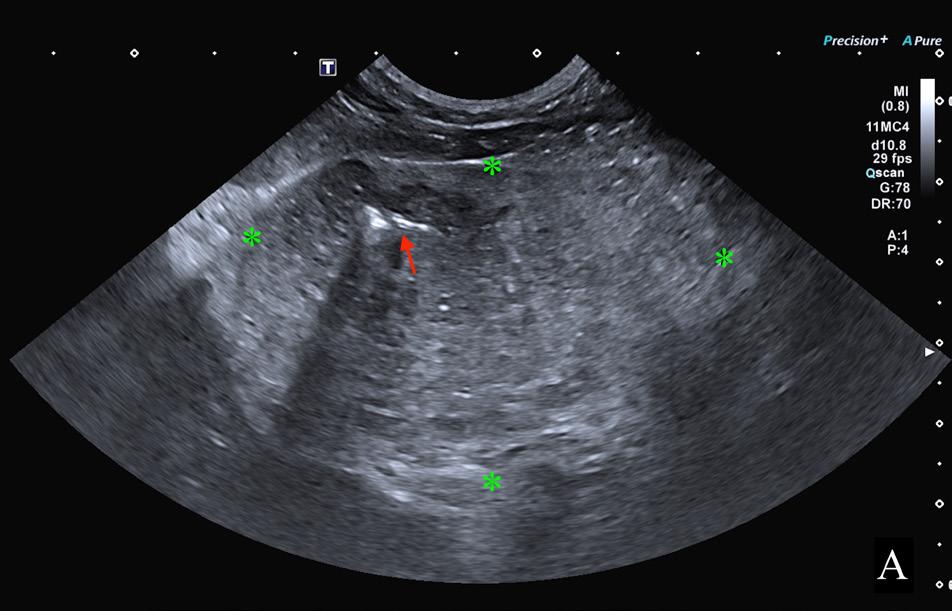

En el presente caso, se realizó una ecografía abdominal donde se identificó la presencia de una masa hepática, heterogénea y de bordes poco definidos, de

Figura 2. Imágenes ampliadas de las radiografías en proyección lateral izquierda (A) y ventrodorsal (B). Se observa la lesión de opacidad gas y bordes irregulares localizada en la proyección hepática, en su aspecto craneoventral y lateralizada a la derecha (flechas blancas). Se muestra otra lesión de opacidad gas, de menor tamaño respecto a la descrita, en la zona media del hígado (flechas moradas), que provoca un efecto masa (*) y genera un desplazamiento hacia caudal del antro pilórico y cuerpo gástrico (flechas negras). Caudoventral a la silueta hepática se observan pequeñas burbujas de gas libre compatible con neumoperitoneo (flechas azules).

8,2 x 6,1 cm, localizada en el aspecto ventral derecho y medio del hígado, con mineralizaciones diminutas y presencia de focos ecogénicos que provocaban artefacto de reverberación compatible con gas intralesional (Fig. 3A); así como otro nódulo hipoecoico de 2,8 x 2,7 cm (Fig. 3B). Además, en el aspecto craneal de los lóbulos hepáticos derechos, se encontró una lesión cavitada, con gas en su interior (Fig. 3B) y múltiples acúmulos de gas intravascular adyacentes a la lesión (Fig. 3C). También se observó un pequeño volumen de líquido libre ecogénico entre los órganos abdominales, gas libre y reacción peritoneal adyacente al hígado.

Se realizó una abdominocentesis ecoguiada que confirmó una peritonitis séptica. Con estos hallazgos, el diagnóstico presuntivo fue de dos abscesos asocia-

Figura 3. Imágenes ecográficas del parénquima hepático mostrando diferentes lesiones. (A) Se observa una masa hepática (*) con presencia de gas intralesional (flecha roja). (B) Lesión hepática con gas en su interior que produce artefacto de reverberación (flecha roja) y un nódulo hipoecoico y bien delimitado (*). (C) Se aprecian múltiples acúmulos de gas intraparenquimatosos a nivel intravascular (flechas rojas).

dos a masas hepáticas con posible rotura, peritonitis y neumoperitoneo, así como hepatitis enfisematosa concurrente.